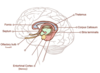

Label the major component parts of the limbic system

Label these structures of the brain

Label this diagram of the brain

Label the structures involved in the hippocampal formation

Tell me about the Trisynaptic circuit in the limbic system

what is it made up of?

- Trisynaptic Circuit: 3 interconnected afferent pathways, taking information into the hippocampus for processing – memory retrieval

- Consists of 3 cell groups: (all distinct neuron types even though called cells)

- Granule cells in DG

- Pyramidal cells in CA3

- Pyramidal cells in CA1

All 3 are excitatory neurons

What 3 synapses are present in the trisynaptic circuit?

(synapse 1) Entorhinal Cortex → DG via the perforant path

(synapse 2) DG → CA3 via mossy fibres

(synapse 3) CA3 → CA1 via Schaffer collaterals (as seen in purple on the diagram)